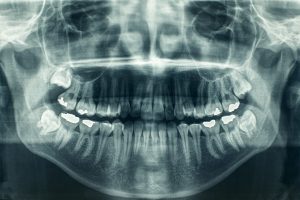

Bone graft procedures are a lot easier than some people think. You will first come in for a consultation and series of x-rays. Next, we will discuss your bone graft options with you and will schedule the procedure. Our highly trained dentist will then make an incision into your jawbone where the bone graft is needed. The bone graft will be placed, and the incision will be closed.